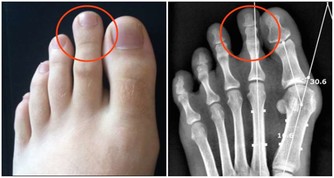

維生素D,又被稱為“陽光”維生素,通常被身體用來保持肌肉、牙齒和骨骼的健康。如果缺乏維生素D,身體很難調節鈣和磷酸鹽的平衡。嚴重缺乏維生素D會導致骨骼畸形,佝僂病,甚至骨軟化症。